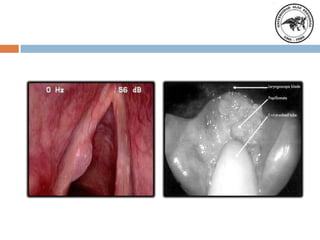

Diagnostico

Laringoscopia

indirecta

y

directa.

Estroboscopia.

Videolaringoscopia

Laringoscopia indirecta, se

visualiza una vibración vocal

asimétrica, con cierre glótico

incompleto. Fibroscopia

Clínicamente por

antecedentes de

intubación reflujo

gastroesofágico.

Laringoscopia indirecta.

Fibroscopia